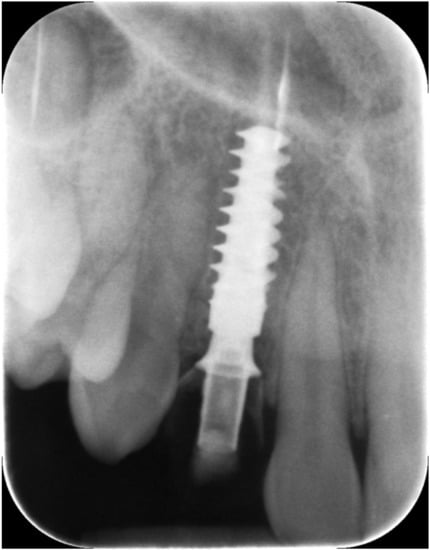

Figure 4.

Immediate temporization of immediately placed implant.

Figure 5.

Periapical X-ray at immediate temporization.